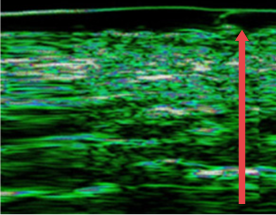

03. Creation of a new blood vessel

It improves blood flow and nourishes the skin by creating new blood vessels.

CD34 Average (Nevascular Indicator)

• radiesse_img10